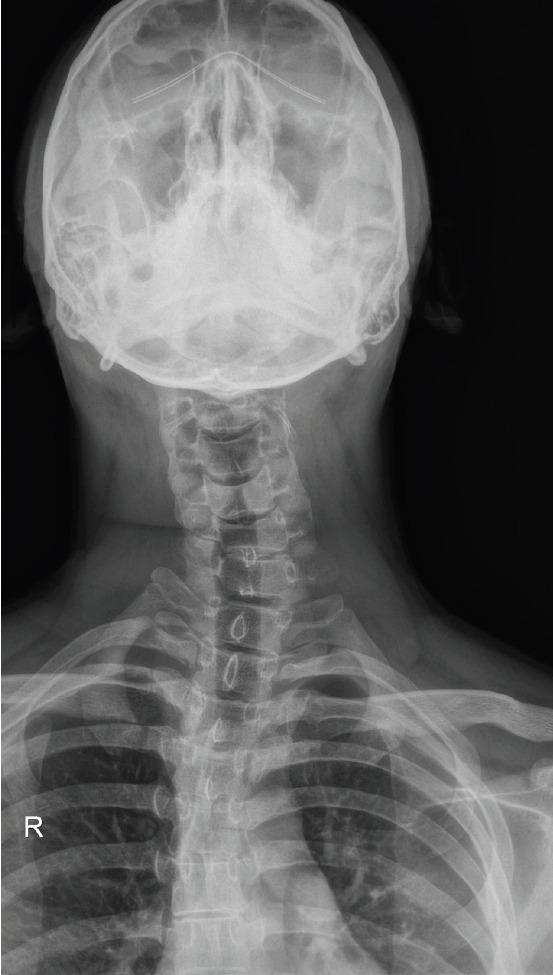

Spondylocarpotarsal synostosis syndrome (SCTS) is a rare genetic disorder characterized by vertebral fusion, short stature, and skeletal anomalies. SCTS is primarily associated with mutations in filamin B. However, in this report, we present a unique case of SCTS in a 28-year-old male who complained of neck and shoulder pain persisting for 1 year. His clinical presentation included radioulnar synostosis, cervical spine anomalies (scoliosis and agenesis of the posterior arch of C1), and a history of polydactyly. Genetic analysis revealed mutations in GMNN and DLL1. To the best of our knowledge, this is the first report on the association of SCTS with these genes.